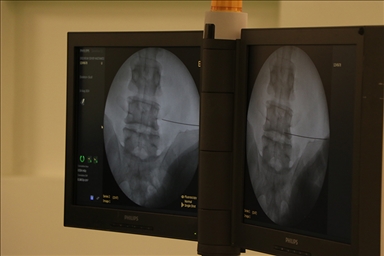

Fıtıkların açık veya son yıllarda sıkça kullanılmaya başlanan laparoskopik yöntemle tamir edilebildiğini belirten Ağalar, şu bilgileri paylaştı:

"Laparoksopik fıtık ameliyatlarında, geleneksel fıtık ameliyatlarındaki gibi karın veya kasıkta büyük cilt kesisi yapmak yerine çok küçük deliklerden içeriye gönderilen kamera ve aletlerin yardımıyla fıtık tamir edilir. Hem açık hem laparoksopik kasık fıtığı onarımlarında nüksü azaltmak için, hastaya herhangi bir zarar vermeyen, ince materyalden oluşan yamalar kullanılır. Laparoksopik ameliyatlarda ağrı az olur, analjezik ihtiyacı azdır. Hastalar daha erken ayağa kalkar ve günlük işlerini yapabilir hale gelir. Laparoskopik kasık fıtığı ameliyatı, prostat, böbrek, safra kesesi sorunları nedeniyle laparoskopik ameliyat olacak hastalarda, aynı seansta, diğer ameliyatla birlikte rahatlıkla uygulanabilir."